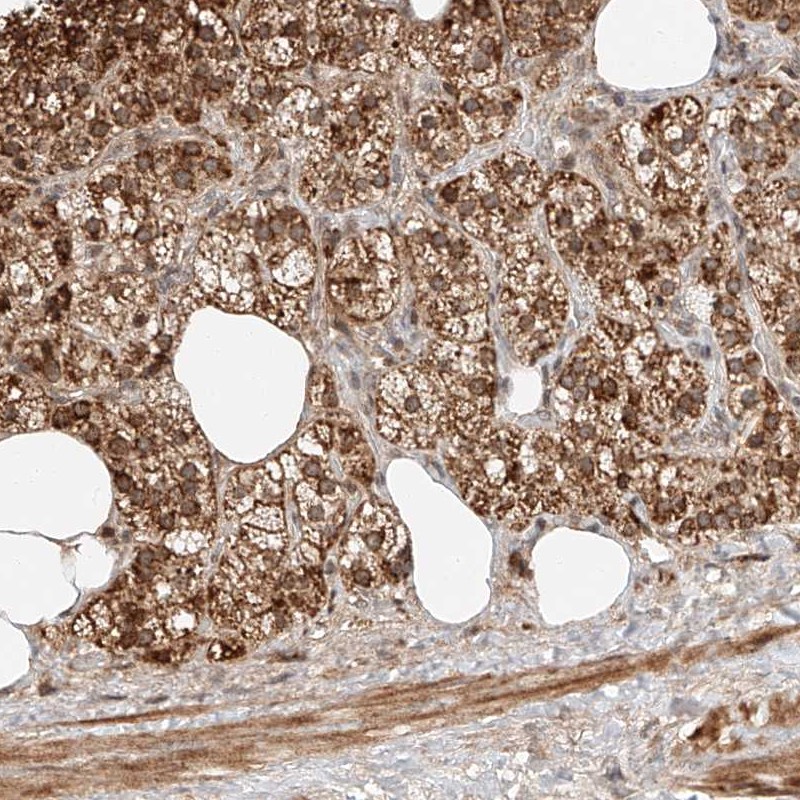

Immunohistochemical staining of human adrenal gland shows cytoplasmic positivity in cortical cells.